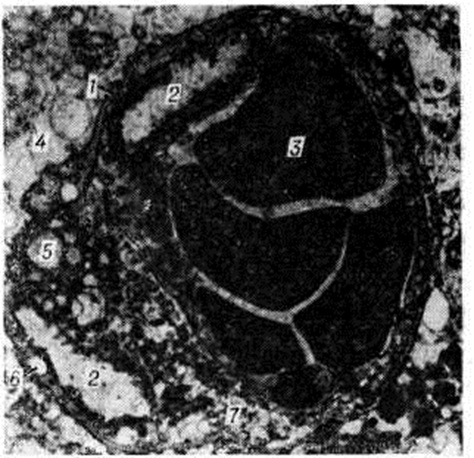

Геморрагический инсульт, как правило, возникает при заболеваниях, протекающих с повышенным артериальное давление. Это обусловлено тем, что сосудистые кризы (смотри полный свод знаний), характерные для гипертонической болезни (смотри полный свод знаний) и артериальной гипертензии (смотри полный свод знаний Гипертензия артериальная), приводят к морфологический изменениям стенок внутримозговых сосудов с нарушением их проницаемости — плазматическому пропитыванию (рисунок 1), некрозам (рисунок 2), образованию микроаневризм (рисунок 3) и их разрывам. Разрыв врождённых артериальных и артериовенозных аневризм может протекать на фоне нормального давления. Преимущественная локализация и характер геморрагий определяются особенностями ангиоархитектоники различных отделов мозга. При гипертонической болезни наиболее тяжёлым изменениям подвергаются сосуды подкорковых узлов и зрительного бугра. Это объясняется отхождением глубоких ветвей под прямым углом от средней мозговой артерии, являющейся продолжением внутренней сонной артерии, и незначительным числом анастомозов сосудов в этой области. В связи с этим на вскрытии кровоизлияния наиболее часто (40%) обнаруживаются в подкорковых узлах с распространением в прилежащее белое вещество (так называемый латеральные кровоизлияния, то есть расположенные латерально от внутренней капсулы, рисунок 4). Второе место по частоте (16%) занимают обширные кровоизлияния, разрушающие подкорковые узлы, внутреннюю капсулу, зрительный бугор (так называемый смешанные кровоизлияния — рисунок 5). Кровоизлияния в зрительный бугор (так называемый медиальные — рисунок 6) составляют 10%, в мозжечок — 6—10%, в мост мозга — 5% от общего числа внутримозговых геморрагий. Кровоизлияния только в белое вещество полушарий мозга встречаются крайне редко. Подразделение полушарных кровоизлияний на латеральные, медиальные и смешанные имеет особое значение в связи с хирургическим лечением геморрагического Инсульт.

Электронно-микроскопическое исследование коры мозга человека при Инсульт выявляет различные ультраструктурные изменения нейронов, глиальных элементов и капилляров. В ультраструктуре капилляров можно выделить следующие основные патологический изменения: дистрофию стенки капилляра с накоплением в ней лизосомальных включений, липофусциновых гранул, распадом митохондрий, расслоение и вакуолизацию базальной мембраны (рисунок 18). Кроме того, отмечается разрастание и гиперплазия эндотелия. Ультраструктурные повреждения капиллярной стенки сопровождаются разнообразными изменениями из просвета. Обнаруживается ряд изменений основных субмикроскопических компонентов нейронов. Наиболее характерны нейроны, изменённые по гиперхромному типу (рисунок 19), что сочетается с пикнозом ядра, разрушением митохондрий, деструкцией гранулярного и агранулярного ретикулума, наличием большого числа вакуолей и лизосомальных включений, и нейроны с явлениями хроматолиза (рисунок 20), который сопровождается исчезновением цитоплазматических включений, растворением мембранных структур, образованием вместо цистерн ретикулума групп дискретных пузырьков, отсутствием рибосом, набуханием митохондрий, появлением вакуолей. Изменение ультраструктуры капилляров и нейронов сопровождается отёком астроцитарных отростков, скоплением тел глиальных клеток вокруг патологически изменённых элементов. В области расположения патологически изменённого капилляра наблюдаются клетки-тени (клетки в состоянии кариоцитолиза). Прослеживается зависимость изменений элементов одной цепи: нейрон — капилляр — глия.